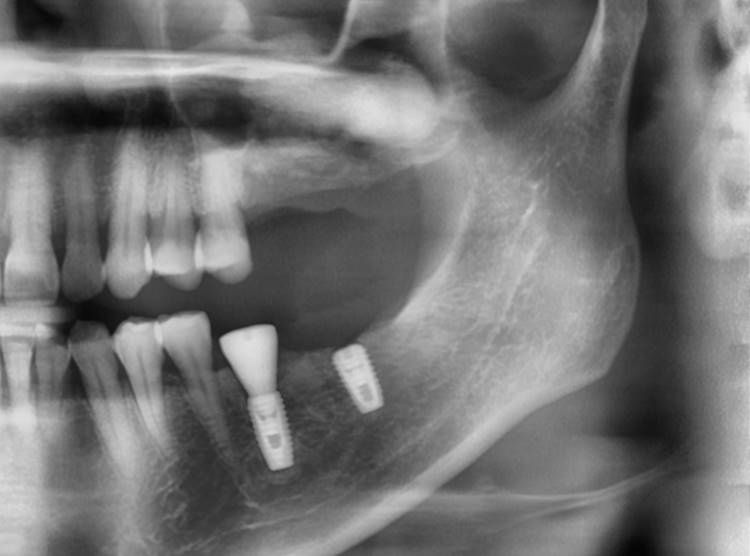

▲. Panoramic radiograph after implant placement in the maxilla.(3 weeks after implant placement in the mandible)

▲Panoramic radiograph after 1 year of the crown delivery.